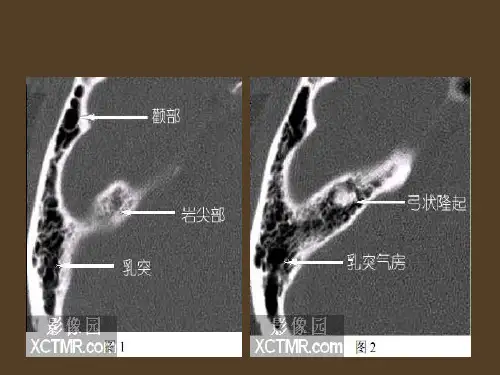

耳部应用解剖生理一、耳部解剖人的耳朵是一个复杂的器官,由外耳、中耳和内耳组成。

1. 外耳:外耳包括耳廓和外耳道。

2. 中耳:中耳是位于鼓膜后面的空腔,它包括鼓膜、鼓室和听小骨。

3. 内耳:内耳位于颅骨内部,包括耳蜗、前庭和半规管。